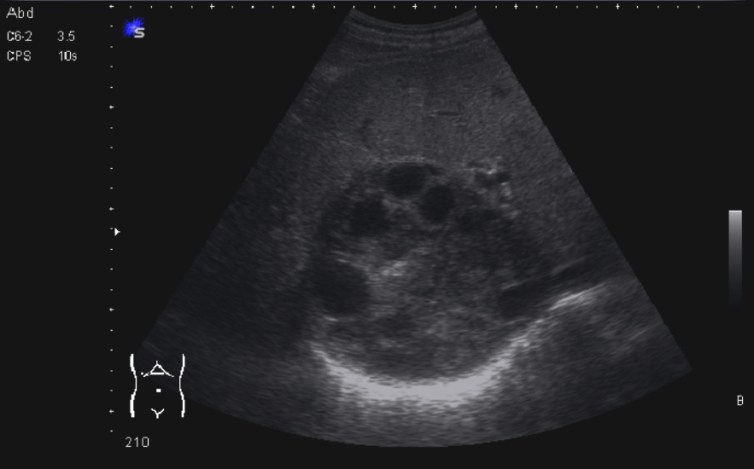

Bien, hemos visto una lesión que es un quiste hidatídico calcificado, pero te preguntarás, si nunca viste uno, ¿cómo es uno cuando tiene «hijas»?, es decir, cuando está activo…Mira este corte transversal de un hígado:

La LOE es de aspecto redondeado, heterogéneo, con multitud de pequeñas imágenes anecoicas e hipoecogénicas, de diferentes tamaños. Esta lesión fue estudiada también mediante otra técnica de imagen, la RMN donde se observa una imagen hiperdensa, con una amalgama de lesiones bordeando a periferia de la misma, de distintos tamaños como se objetiva en la imagen del mismo paciente, de la ecografía inmediatamente superior (Imagen 7). La lesión es activa, por tanto debió de ser tratada, la patología es potencialmente mortal en caso de que el quiste se rompiese.